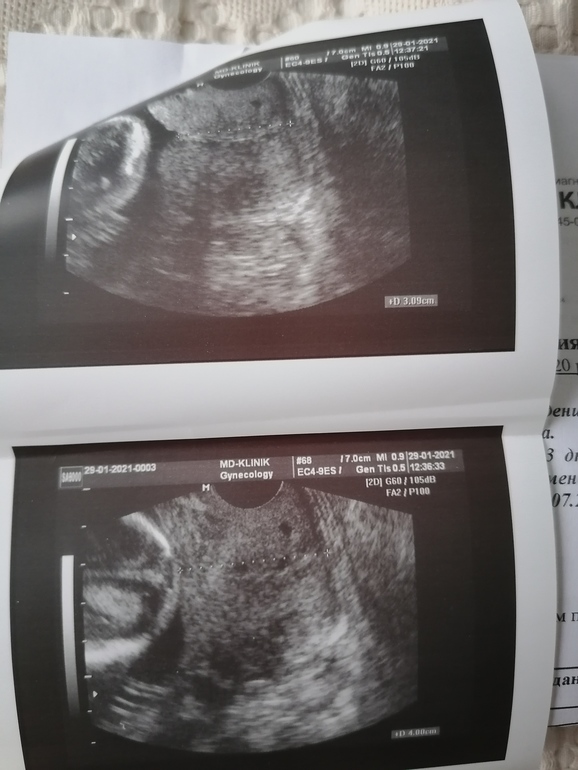

Сходила сегодня на приём к врачу, должна была в воскресенье планово, но боли меня доканали. И не зря пошла тонус сильный, сынок зажат там. И шейка сильно реагирует на тонус без него 40мм, а при тонусе 31 и внутренний зев приоткрывается. Вообщем выписали мне утрик вставлять утром и вечером и на ночь папаверин. Буду верить, что шейка не подведёт в этот раз. В 5 и 6 беременность стоял пессарий.

Тут видно как шейка себя ведёт при тонусе фото сверху и без фото снизу.